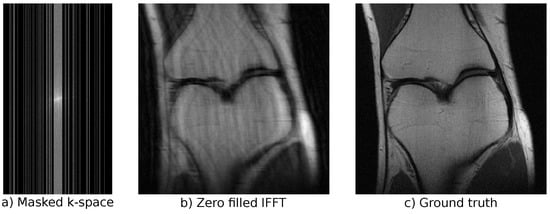

3.3. Magnetic Resonance Imaging

4.3.1. Base Distribution